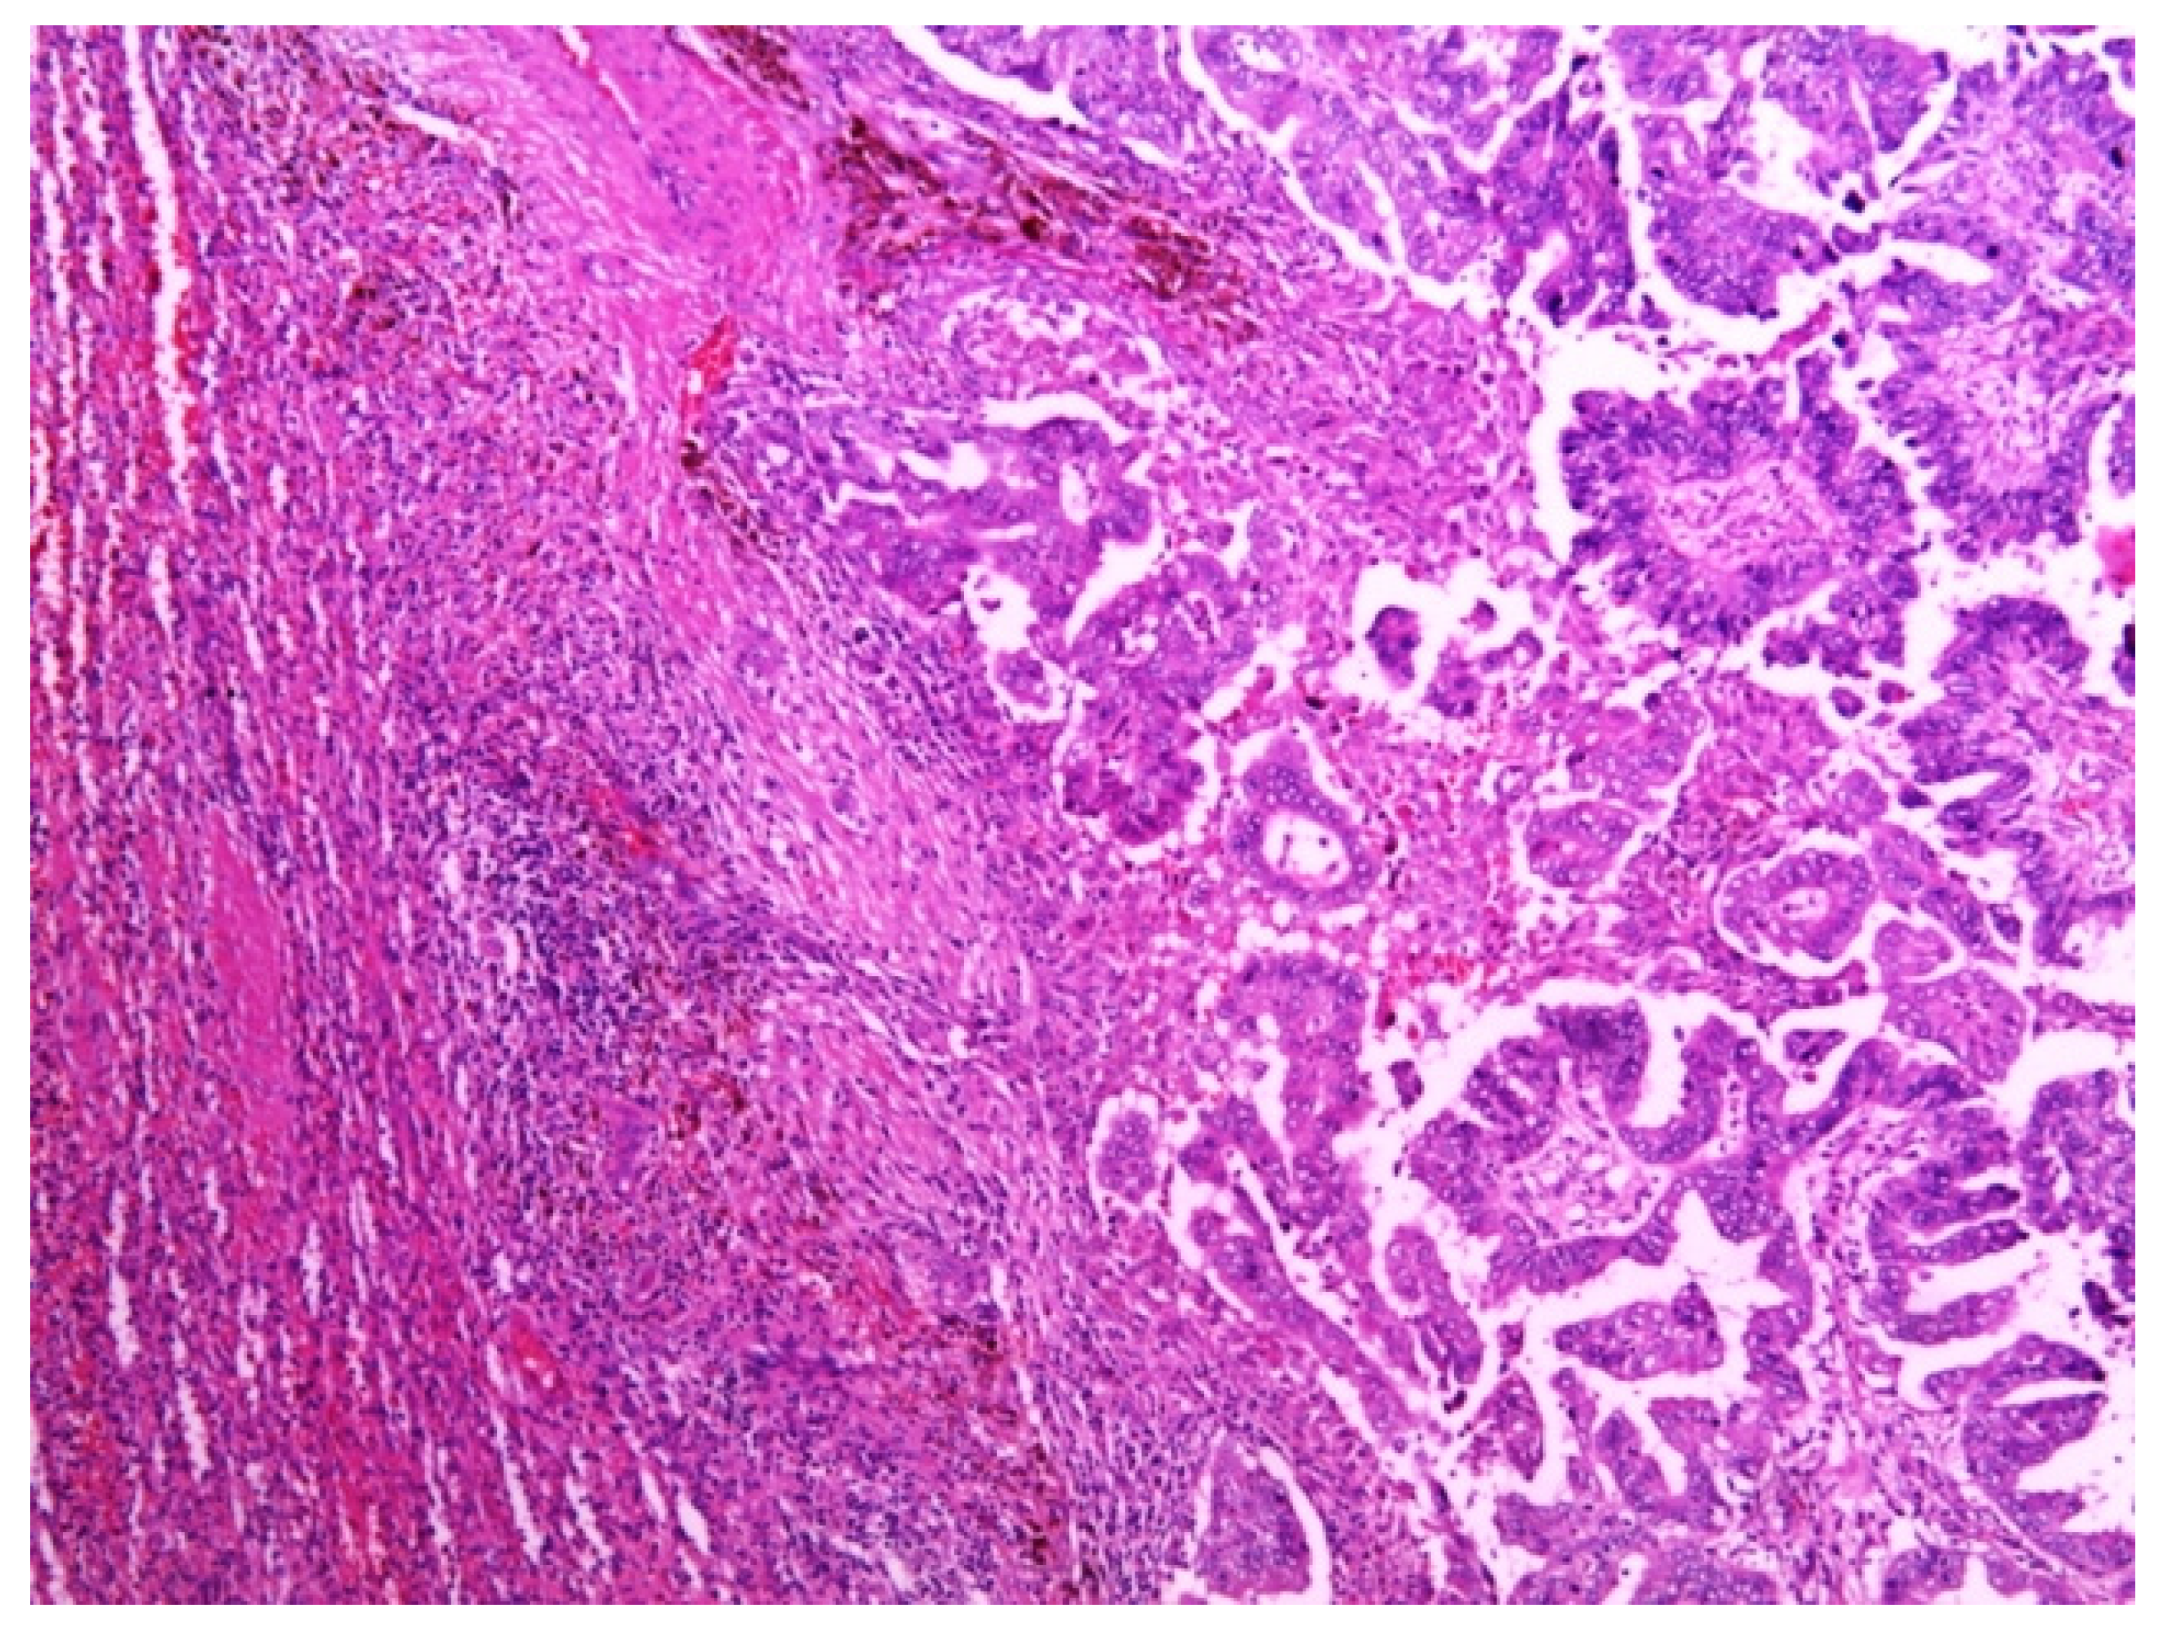

3. Multidisciplinary Expert Consultation and Final Diagnosis

4. Treatment